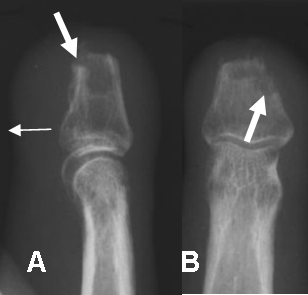

En las fijaciones la infección se descubre por la aparición de zona lítica y mal definida, rodeando el material de osteosíntesis. Debe diferenciarse del aflojamiento del material, el cual presenta bordes irregulares y escleróticos. (16). (Fig 47A y 47B).

Fig 47 A. Osteomielitis PostQx.

A: Rx lateral y B: Rx AP. Amputación traumática de la falange media en el 3 dedo. Por persistencia del dolor se toma Rx encontrando gran edema de tejidos blandos (Flechas delgadas), irregularidad de los bordes óseos y área de osteolisis, por osteomielitis. (Flecha gruesa).